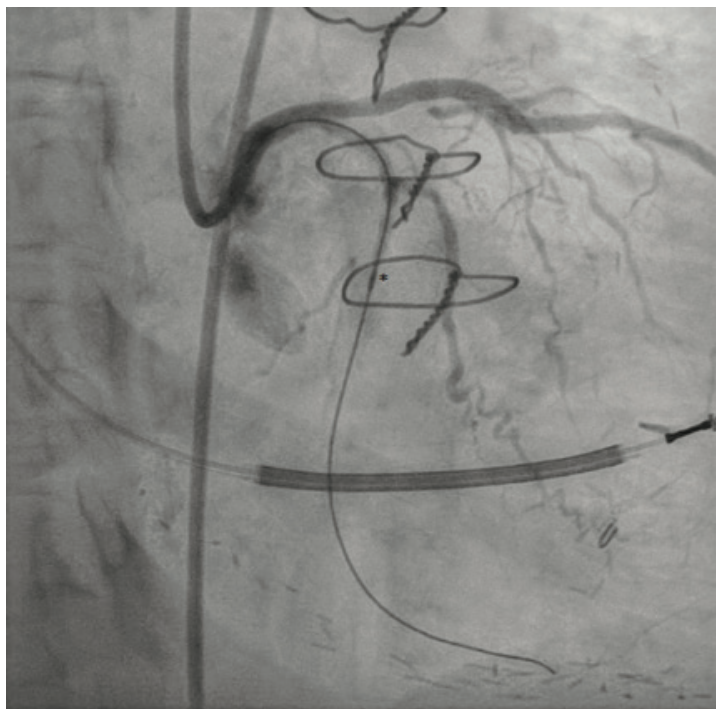

A Takeru 1.5 mm x 6 mm PTCA balloon was subsequently easily able to cross into the distal vessel and dilate the lesion with multiple inflations (Figure 6). After further predilation with larger PTCA balloons, technical success was achieved after successful placement of two Orsiro Mission drug-eluting stents (Biotronik) (Figure 7).